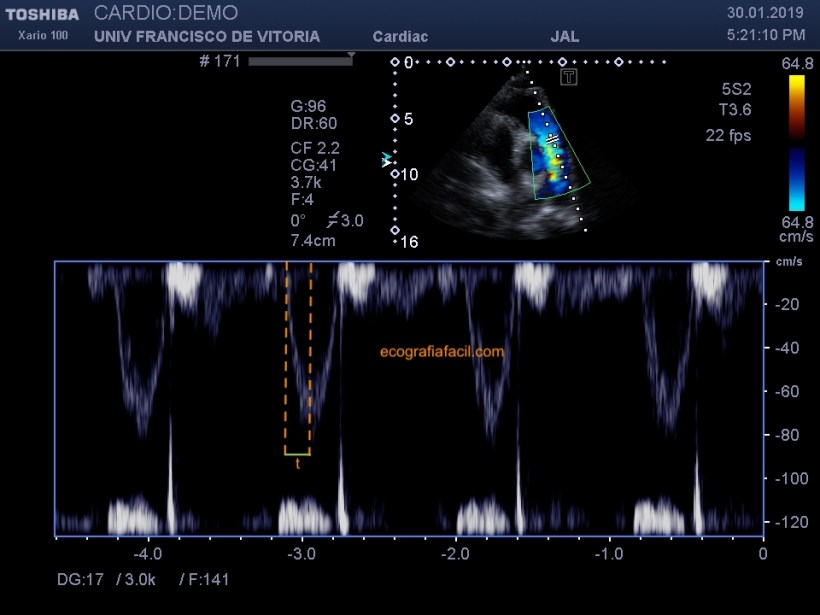

También podemos poner el color sobre la válvula tricúspide y, en caso de observar una regurgitación, pasar el Doppler espectral continuo (recuerda que el CW es algo casi exclusivo de la cardio) para medir la velocidad máxima de la regurgitación. Esta medida será importante para cuantificar después si existe o no hipertensión pulmonar.

We can also put the color on the tricuspid valve and, in case of observing a regurgitation, pass the continuous spectral Doppler (remember that the CW is something almost exclusive of cardio) to measure the maximum speed of regurgitation. This measure will be important to quantify later whether or not pulmonary hypertension exists.